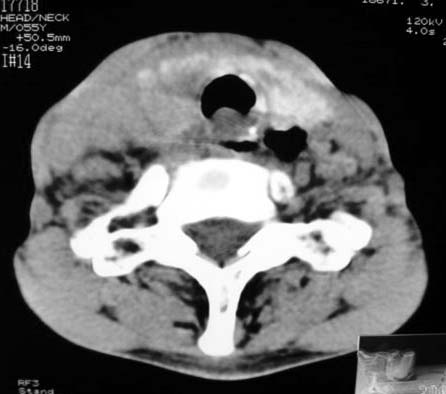

以下是引用dyqct在2007-4-20 16:19:00的发言:[br]考虑:1、左侧梨状窝区破裂伴左颈深、浅部气肿。[br] 2、右侧甲状腺区血肿(请追问病史是否伤及右颈部)。[br] 3、建议病情稳定后增强扫描除外右侧甲状腺腺瘤。